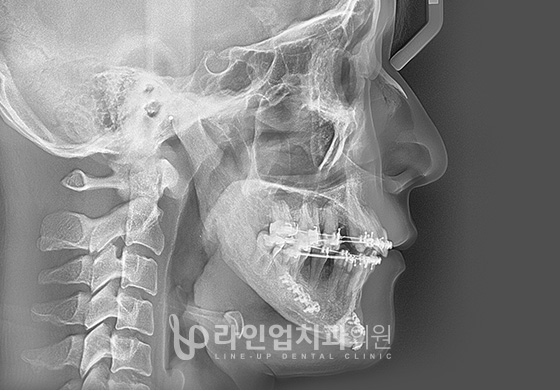

The lower jaw is cut between the jawbone and the jaw joint at the back of the molar.

Move to the normal position as a plan.

Secure the chin with a tool.

Before and After

Before